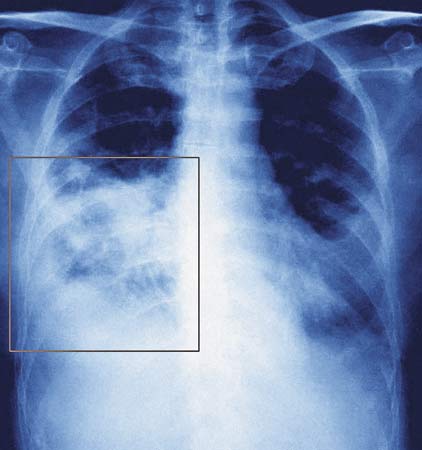

В анализе крови наблюдается воспалительная реакция - увеличение лейкоцитов (белых кровяных телец), сдвиг лейкоцитарной формулы влево, повышение уровня СОЭ. С целью выявления бактериальной инфекции и ее идентификации берут анализ мокроты при ее откашливании. Исследование мокроты необходимо производить вскоре после ее забора. Информативным диагностическим методом является рентгенографический, при котором визуализируется очаг воспаления в виде затемнения части легочного поля.